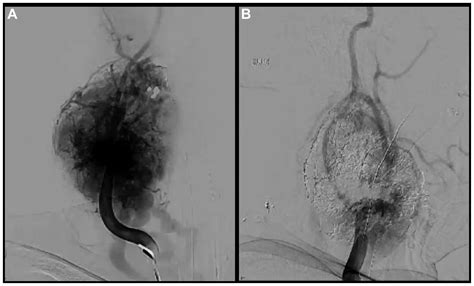

Catheter Angiography The "gold standard" for identifying the blood supply and planning potential embolization.

The primary treatment for a Carotid Body Tumor is surgical resection. Due to the high vascularity of the tumor, surgeons often perform preoperative embolization, which involves injecting a substance into the tumor’s blood vessels to block the supply. This step significantly reduces the risk of excessive bleeding during the main operation.